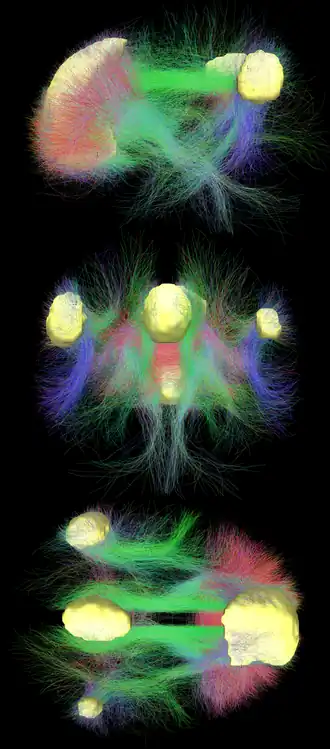

- Graphik der Verbindungen: Strukturelle Verbindungen, die das DMN unterstützen. a entspricht den Assoziationsbahnen, die die kortikalen Regionen des DMN verbinden. b veranschaulicht die Projektionsbahnen, die die Verbindungen zwischen subkortikalen und kortikalen Regionen des DMN vermitteln, aus media.springernature.com [16], Alves, P.N., Foulon, C., Karolis, V. et al. An improved neuroanatomical model of the default-mode network reconciles previous neuroimaging and neuropathological findings. Commun Biol 2, 370 (2019). https://doi.org/10.1038/s42003-019-0611-3, auf www.nature.com [17]